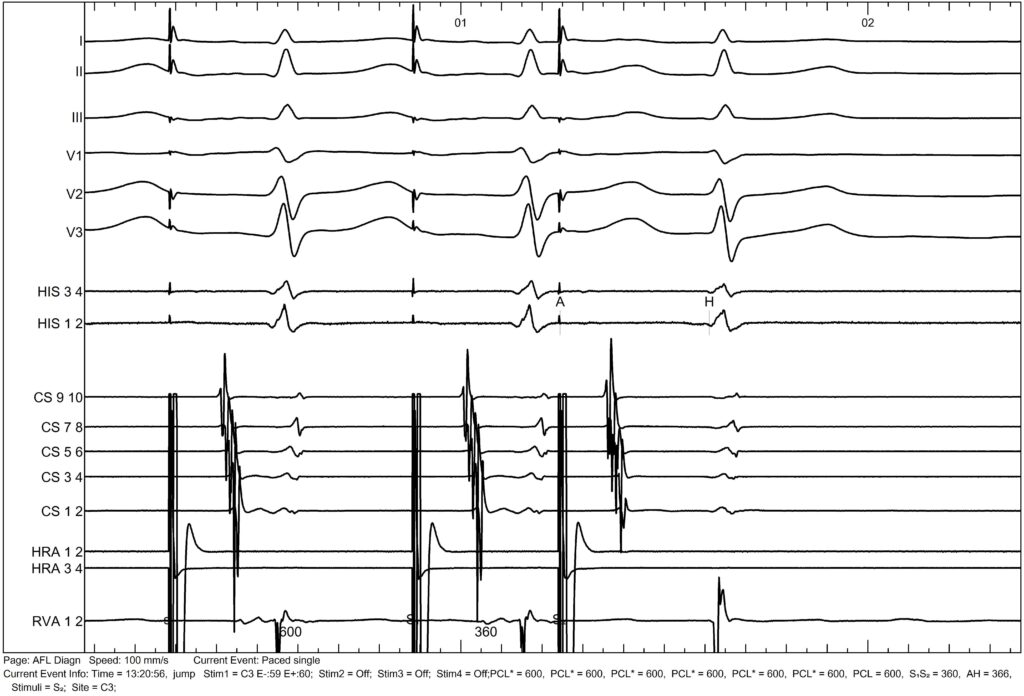

Here, we are pacing the HRA with an extra stimulus, and we observe a jump when moving from an extrastimulus of 370 ms to 360 ms.